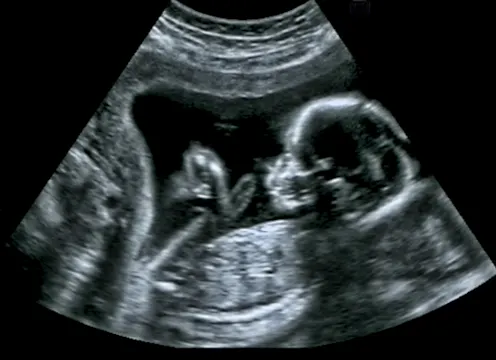

The UK has the fourth highest prevalence of drinking in pregnancy in the world. This puts a significant number of people at risk of a group of conditions known as foetal alcohol spectrum disorder (FASD). Until now, though, the prevalence of FASD in the UK has not been known.

For our study, we followed the development of 13,495 children born in the west of England in the early 1990s. Using a wide range of information on their development and their mothers’ reported drinking in pregnancy, we developed a screening tool and found that up to 17% of children had features consistent with FASD.

This means that these children had evidence of being exposed to alcohol in pregnancy and had problems with at least three different areas of learning and behaviour. Some children also had physical features of FASD, including below average growth and distinctive facial features (small eyes, smooth philtrum and a thin top lip). Most, however, did not show these physical signs. This suggests that FASD could be a relatively hidden disability.